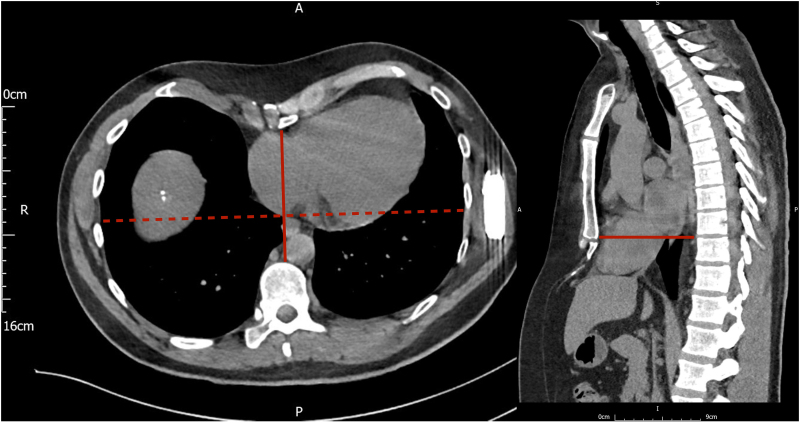

Figure 2.

Pre-operative computed tomography scan—pre-operative computed tomography scan for surgical planning, demonstrating the degree of pectus excavatum; axial view (left) and sagittal view (right).

Pre-operative planning with a computed tomography (Figure 2) clarified the degree of pectus excavatum and anatomical landmarks, and the procedure was performed under a general anaesthetic. The S-ICD was first explanted without complication. Anatomical landmarks for the EV-ICD were marked, and then, an incision was made inferior to the xiphisternum to access the substernal space. Blunt dissection was performed to reach the pre-rectus plane, rectus muscle, and finally through the diaphragm. Particular care was taken to ensure access was made into the mediastinal rather than pericardial or pleural spaces. The Epsila EV™ sternal tunnelling tool was carefully advanced superiorly within a SafeSheath® peel-away sheath, with sequential orthogonal fluoroscopic views confirming the correct course (Videos S1 and S2). On lateral fluoroscopic projections, the pectus caused distortion of the view, giving a misleading impression of the tunnelling tool. Particular care was therefore taken to angle the tunnelling tool away from the pericardium, by maintaining contact with the posterior sternum. The tunnelling path was then extended to the upper border of the cardiac silhouette. Once in place, the tunnelling tool was removed, and the lead was advanced via the peel-away sheath.